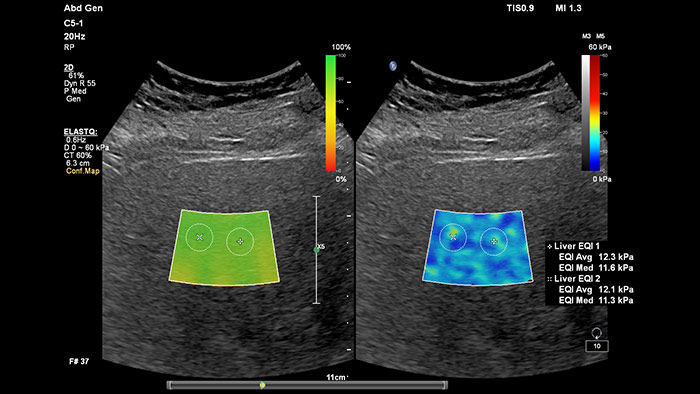

Elastografía por onda transversal de imágenes con ElastQ

La elastografía por ultrasonidos de onda transversal ofrece un método no invasivo, reproducible y fácil de poner en práctica para evaluar la rigidez tisular. Los estudios realizados apuntan a que, en lugar de un costoso y doloroso procedimiento de biopsia, una sencilla exploración por ultrasonidos con elastografía de onda transversal podría convertirse en el procedimiento habitual para evaluar el estado de las enfermedades hepáticas.  La elastografía por onda transversal de alto rendimiento de las imágenes con ElastQ incluye la evaluación cuantitativa de la rigidez tisular, codificada con colores, en extensas regiones de interés (ROI) en tiempo real.  Las imágenes con ElastQ también ofrecen la posibilidad de efectuar mediciones retrospectivas en imágenes almacenadas; además, una exclusiva pantalla con un mapa de confianza emplea el análisis inteligente para ofrecer la garantía adicional de que las mediciones del usuario se han obtenido en zonas tisulares con una propagación adecuada de ondas transversales.

Evaluación hepática no invasiva simplificada

La medición de la rigidez hepática se obtiene en cuestión de segundos por medio de una sencilla exploración no invasiva.